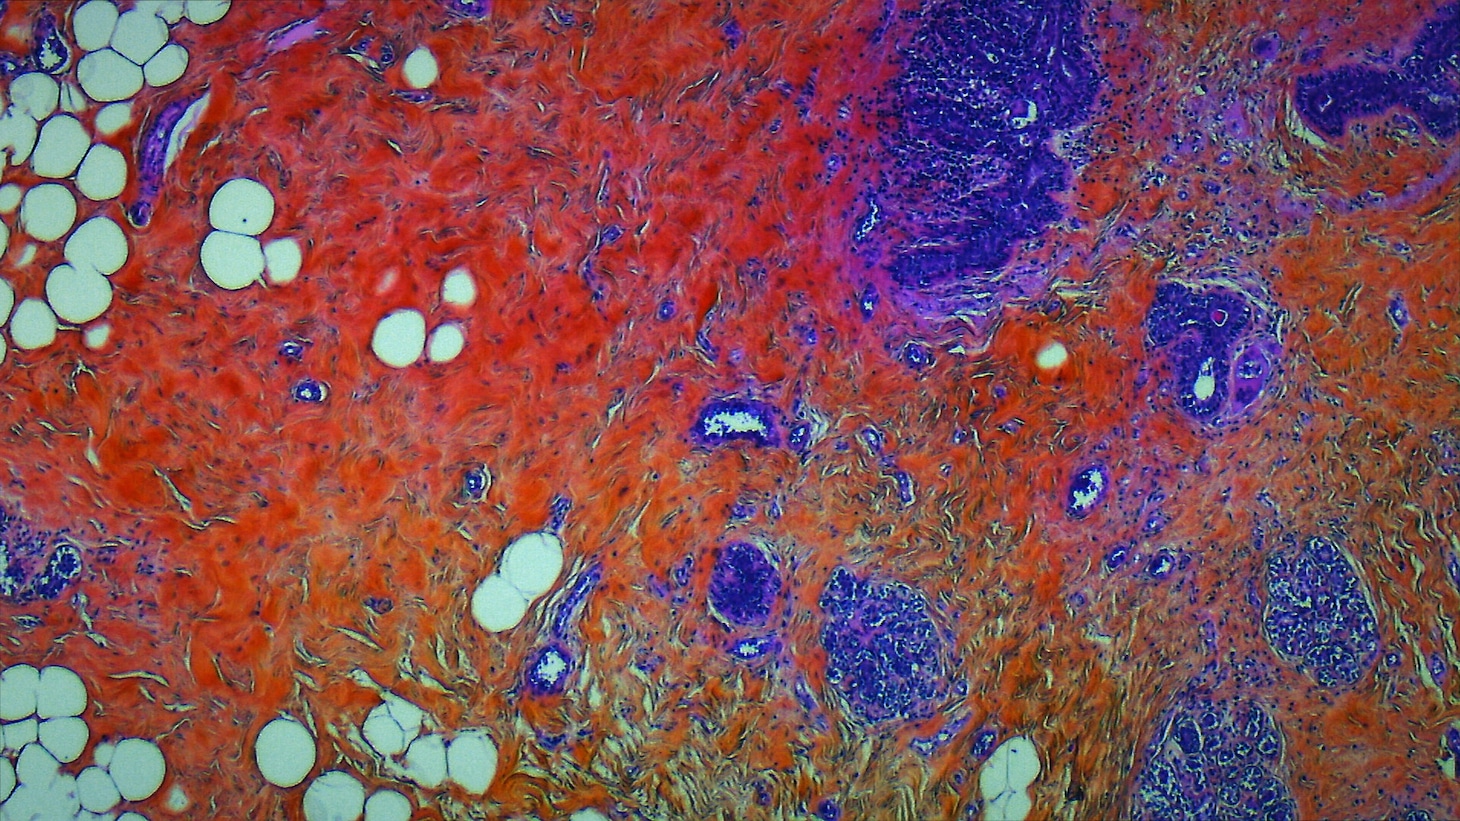

人体の神秘がテーマ、医師の視点で外科手術を見つめるドキュメンタリーが全国公開(画像・動画ギャラリー 7/8) 前へ 次へ 「人体の構造について」場面写真 [記事に戻る] 前の画像 「人体の構造について」場面写真 次の動画 映画「人体の構造について」特報 この画像のタグ 人体の構造について この記事の画像・動画(全8件) この画像のほかの記事 「人体の構造について」本予告が公開、伊藤潤二「手術映像はまるでイリュージョン」 (c)Norte Productions - CG Cinéma - S.E.L - Rita Productions - 2022 × 118 この記事に関するナタリー公式アカウントの投稿が、SNS上でシェア / いいねされた数の合計です。 28 62 28 シェア 記事へのコメント(7件) 読者の反応 118 7 熊本アイ/Ai Kumamoto @eye10100 生きてて良かった最高すぎるぜ https://t.co/vLz10pkDkC コメントを読む(7件)